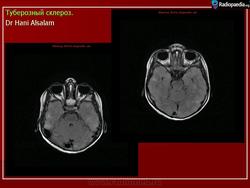

Туберозный склероз, или синдром Бурневиля - Прингля.

Туберозный склероз (болезнь Бурневилля-Прингла, синдром Бурневилля - Брессау) - глиоз белого вещества мозга, проявляющийся в раннем детстве эпилептическими припадками (в 85%), олигофренией в сочетании с нараста­ющей пирамидной и экстрапирамидной симптоматикой, кожной патологией. В возрасте 4-6 лет на лице в форме бабочки в области носа обычно появляют­ся множественные желто-розовые или коричнево-красные узелки диаметром чуть больше 1 мм - аденомы Прингла, которые обычно признаются аденомами сальных желез, однако есть мнение и о том, что они представляют собой про­исходящую из нервных элементов кожи гамартрому.

На поверхности мозга наблюдаются единичные или множественные глиома-тозные узлы, по цвету несколько светлее окружающего мозга и плотнее его на ошупь, возможна их кальцификация. Узлы могут быть и в белом веществе, под­корковых ганглиях, а также в стволе мозга и в мозжечке.

Встречаются и аномалии развития извилин мозга в виде микро- и пахигирии. Заболевание чаще носит спорадический характер. Бляшки достигают диаметра 5-20 мм. В коре больших полушарий и мозжечка иногда могут быть обнару­жены пластинчатые тельца, напоминающие амилоид. Происходит дегенерация клеток коры. При КТ-исследовании головы нередко можно выявить кальцифика-ты и глиальные узелки в паравентрикулярной области, субэпендимарно вдоль на­ружных стенок боковых желудочков, в зоне межжелудочкового отверстия Мон­ро, реже - в мозговой паренхиме. На М РТ головного мозга в 60% выявляются гипотеденсивные очаги в одной или обеих затылочных долях, которые расце­ниваются как участки неправильной миелинизации (Козлов А.В., 2002).